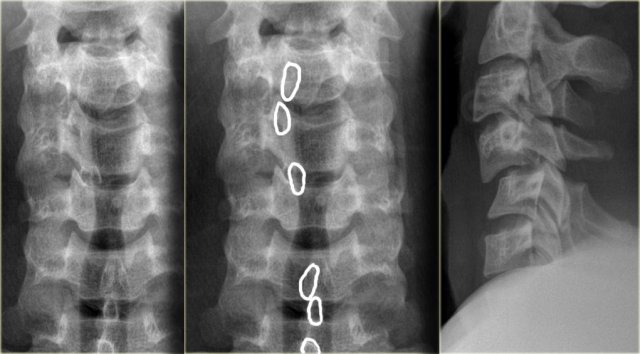

On the left images of a 44 year old female, who sustained a fall on the ice.

She subsequently had a second fall the following morning, where after she had complete loss of motor and sensation.

On physical examination there was lower extremity paraparesis with some upper extremity weakness on the right.

Central cord injury was proposed initially.

The radiographs were normal.

The findings are:

- Small bone fragmets comming off the superior and inferior facets

- Widened interspinous space at C5-6

- Soft tissue swelling at this level posteriorly

- Subtle narrowing of the disc space at the C5-6-level.

These CT-findings are very subtle and do not seem to match the neurological problem.

In such a case MRI is the next step.